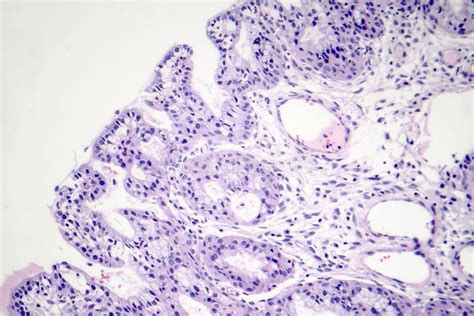

Gallbladder polyps are growths or lesions resembling growths (polypoid lesions) in the wall of the gallbladder. True polyps are abnormal accumulations of mucous membrane tissue that would normally be shed by the body.

Most small polyps (less than 1&#;cm) are not cancerous and may remain unchanged for years.[1] However, when small polyps occur with other conditions, such as primary sclerosing cholangitis, they are less likely to be benign.[2] Larger polyps are more likely to develop into adenocarcinomas.[citation needed]

Cholesterolosis is characterized by an outgrowth of the mucosal lining of the gallbladder into fingerlike projections due to the excessive accumulation of cholesterol and triglycerides within macrophages in the epithelial lining.[3] These ch